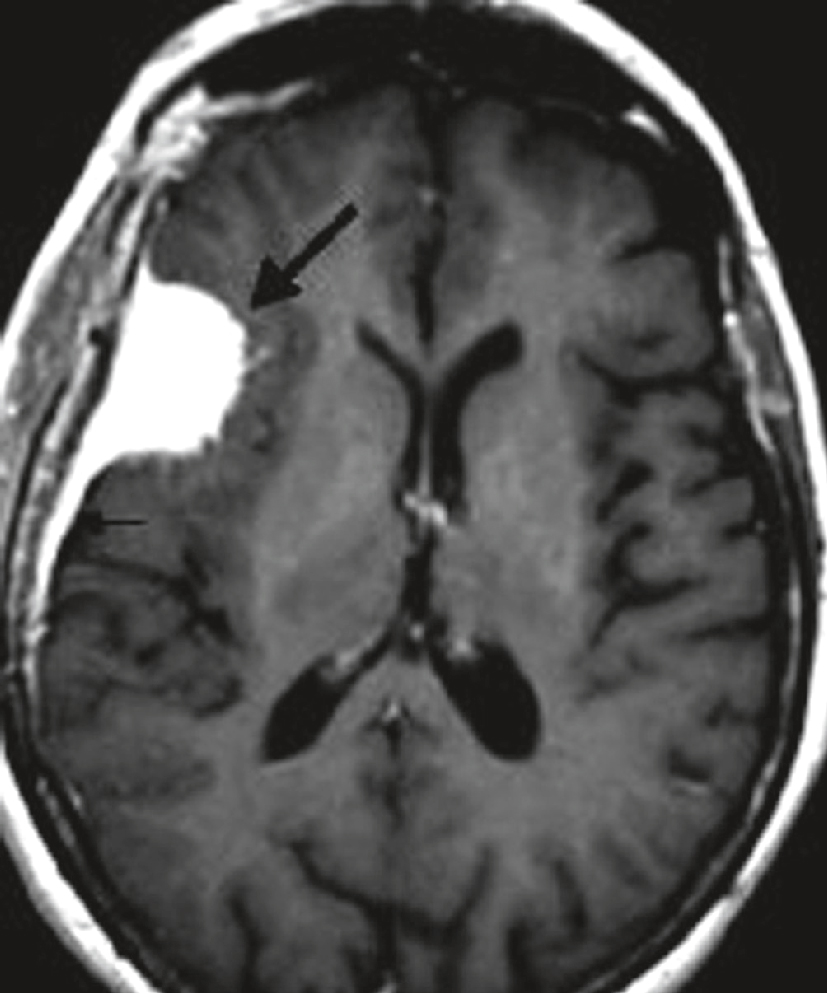

IRM cérébrale chez une femme de 54 ans présentant des crises d’épilepsie partielle depuis 1 mois. Séquence axiale T1 après injection de gadolinium : lésion extracérébrale, refoulant le parenchyme cérébral, bien limitée, à base d’implantation large sur la convexité, prenant le contraste de manière intense et homogène (flèche en gras). Prise de contraste de la dure-mère adjacente (petite flèche) correspondant à la languette d’insertion dure-mérienne du méningiome (image en « queue de comète »).

IRM cérébrale en coupe axiale pondérée en T1 montrant une masse cortico-sous-corticale hyperintense bien délimitée au niveau du lobe frontal gauche, avec un effet de masse sur le ventricule latéral adjacent et une discrète hypodensité périlésionnelle compatible avec un œdème vasogénique. La lésion, indiquée par une flèche épaisse, évoque une tumeur d’allure infiltrante responsable de la déformation des structures avoisinantes. La flèche fine signale un effet de masse modéré sur le cortex adjacent. Le contexte clinique de crises d’épilepsie partielle récentes chez cette patiente de 54 ans renforce la suspicion d’un processus tumoral évolutif, tel qu’un gliome de bas ou de haut grade.